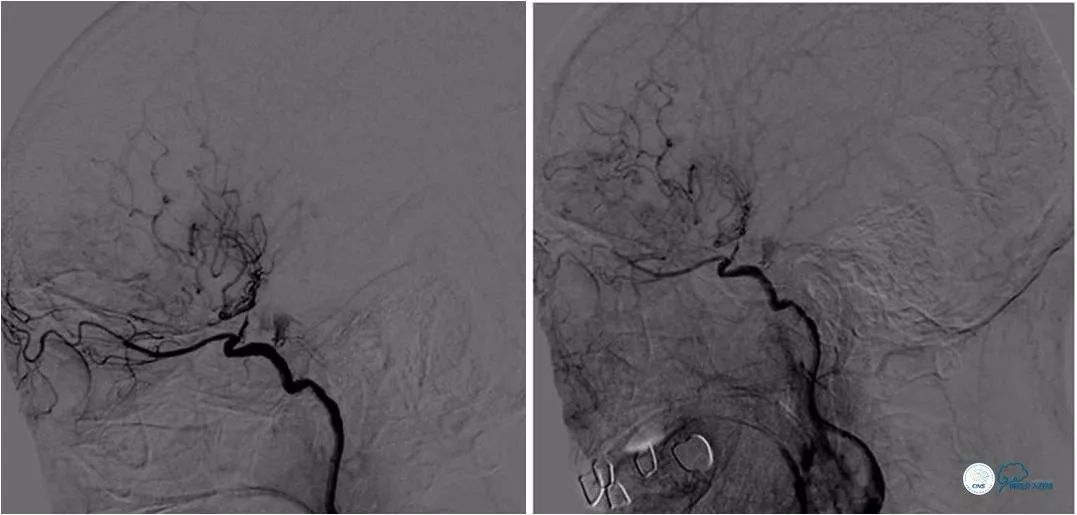

DSA:左颈内动脉C6-7段重度狭窄,狭窄程度重,病变较长,前向血流减慢(图4,5),后循环造影显示后循环向前循环侧支代偿不足(图6)。

图4

图5

图6